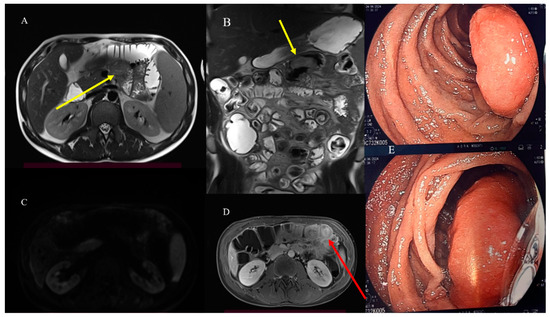

- Pezzella, M.; Brogna, B.; Romano, A.; Torelli, F.; Esposito, G.; Petrillo, M.; Romano, F.; Di Martino, N.; Reginelli, A.; Grassi, R. Detecting a rare composite small bowel lymphoma by Magnetic Resonance Imaging coincidentally: A case report with radiological, surgical and histopathological features. Int. J. Surg. Case Rep. 2018, 46, 50–55. [Google Scholar] [CrossRef]